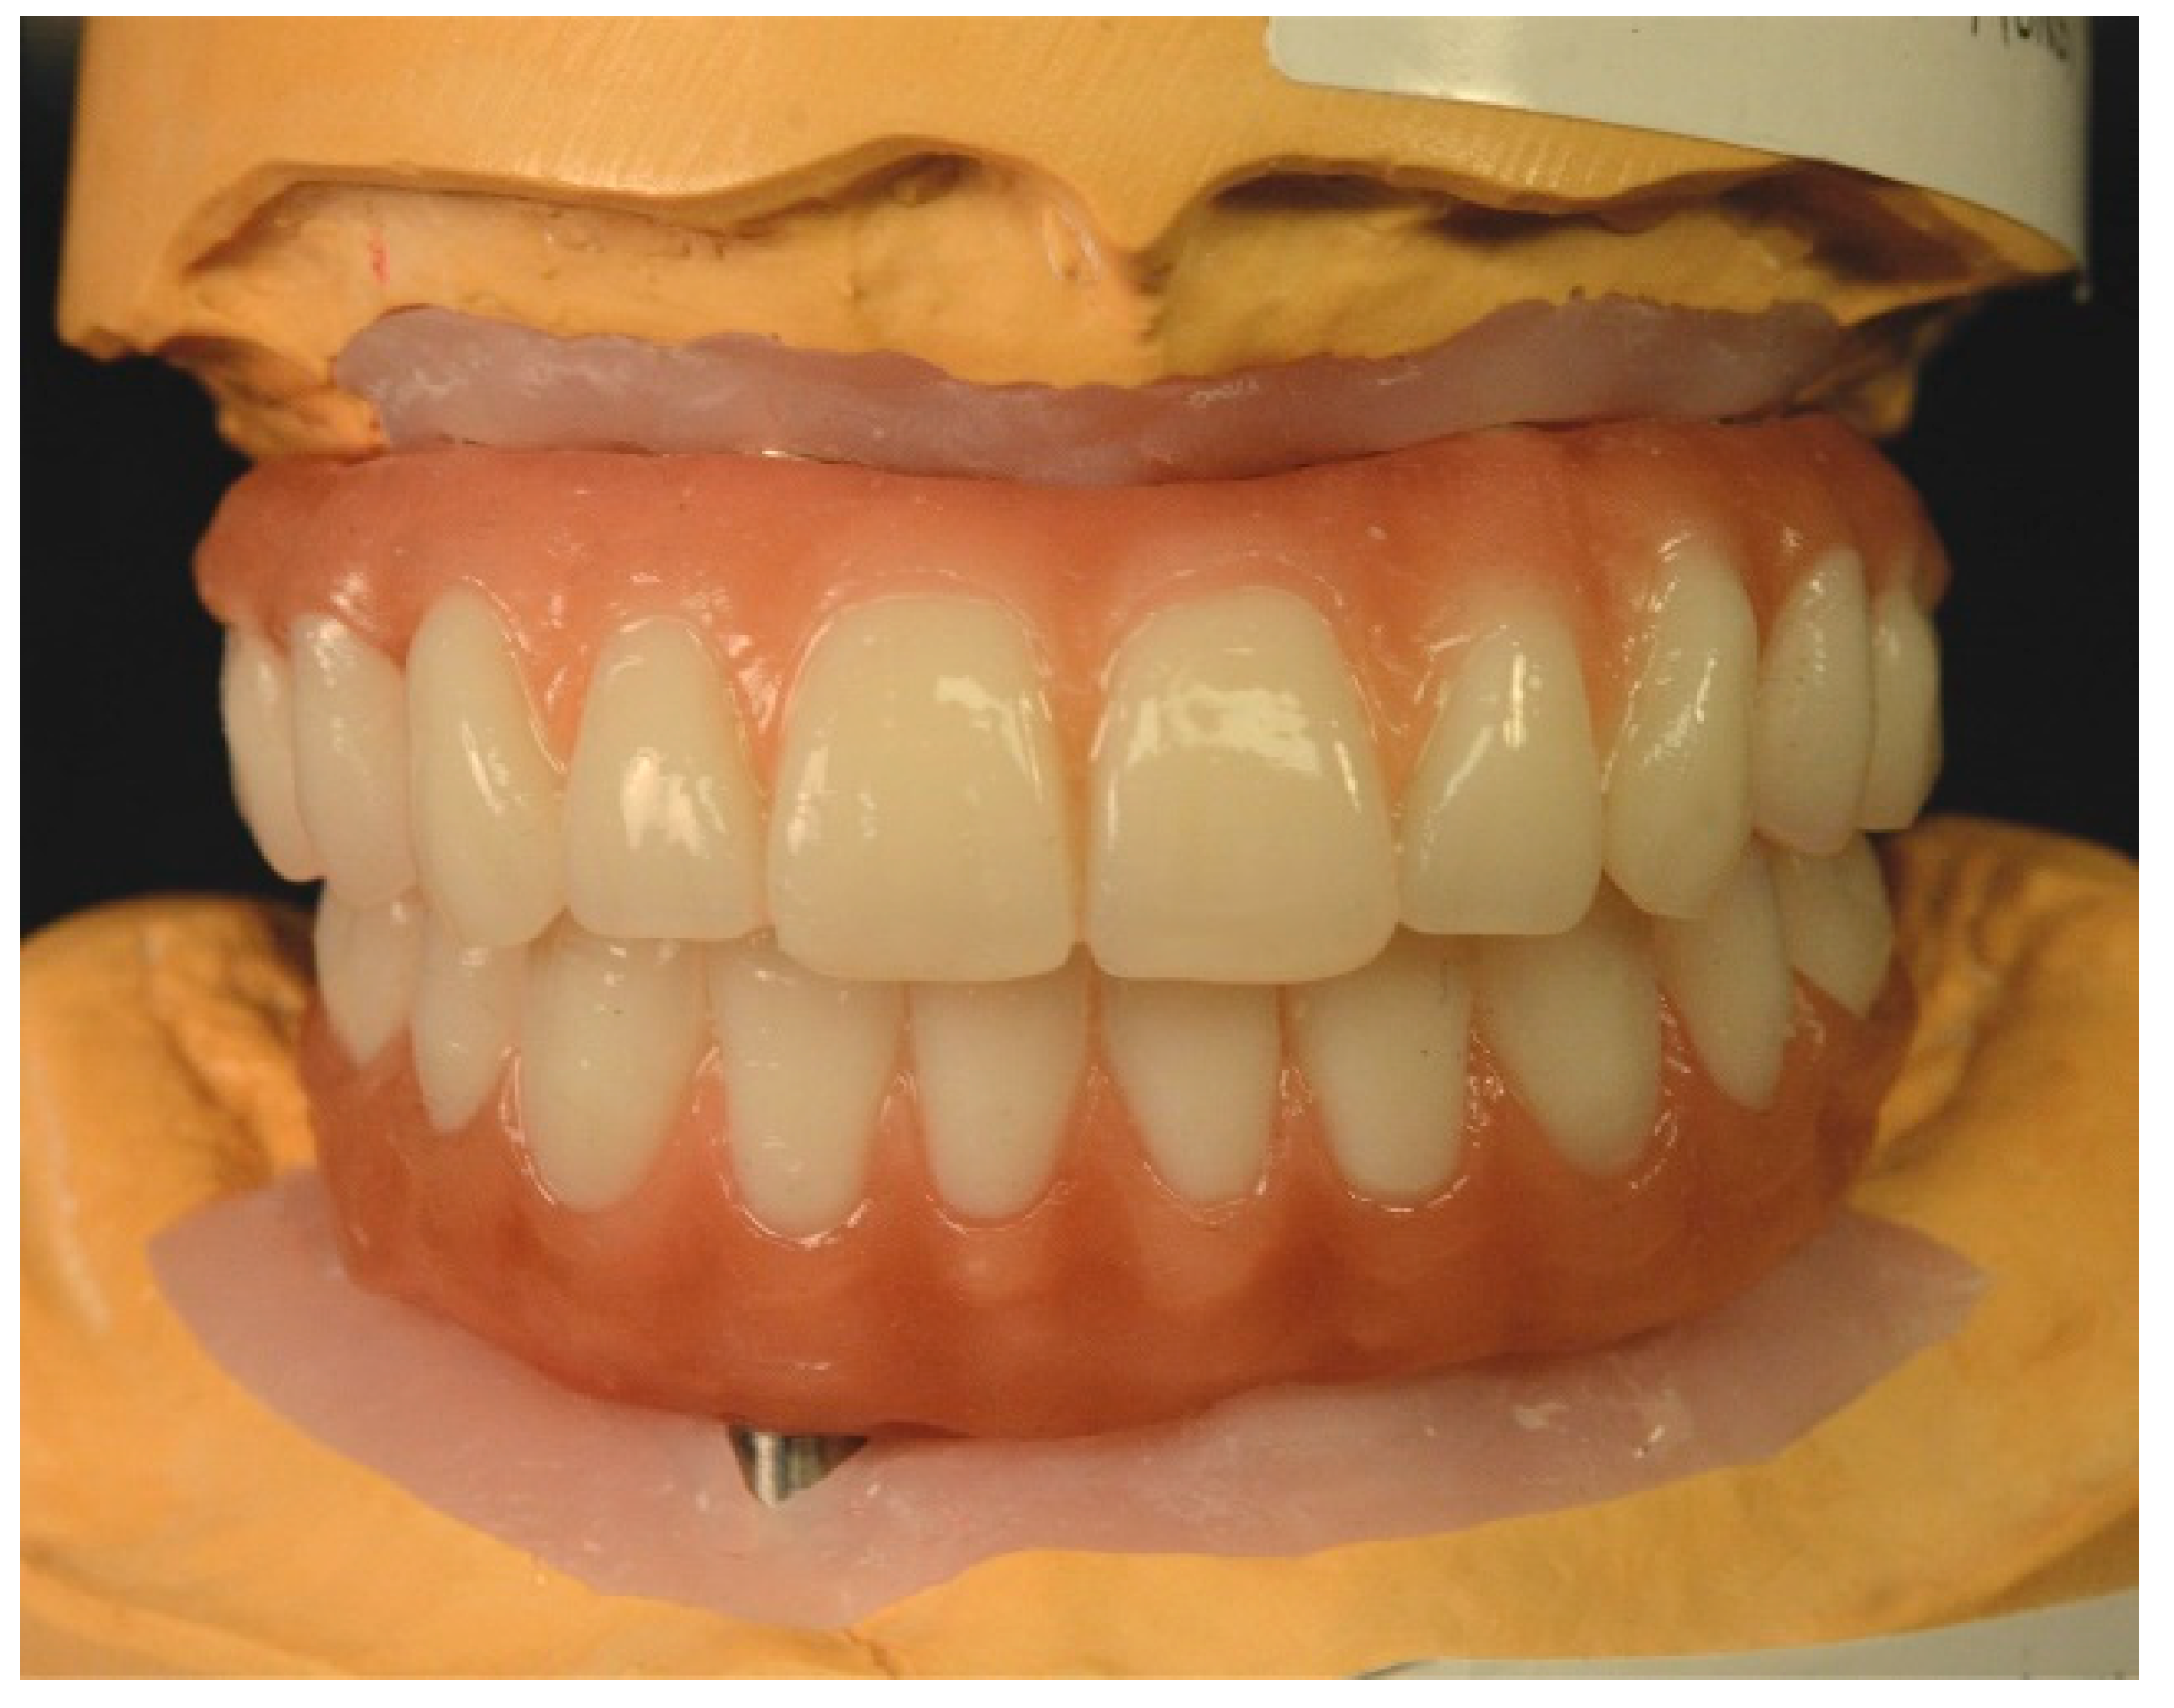

Subsequently, the definitive maxillary and mandibular prostheses were fabricated (Figure 9) and tried intraorally.

Figure 9.

Maxillary and mandibular definitive complete-arch implant-supported prostheses.